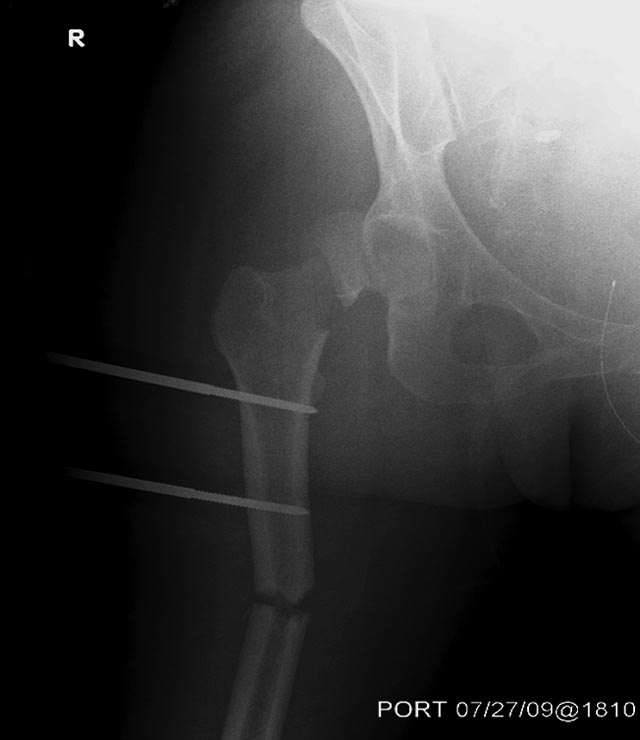

1.Вправление вывиха бедра, репозиция, остеосинтез перелома шейки бедра

3.После компенсации состояния внутренний остеосинтез диафиза и

дистального метафиза правого бедра.

В нашем случае с момента травмы прошло около 2 суток, и переломо-вывих

Во время совместной операции с хирургами по I&D  вакумированием раны

живота и ран конечности, смогли быстро наложить наружный фиксатор на бедро.